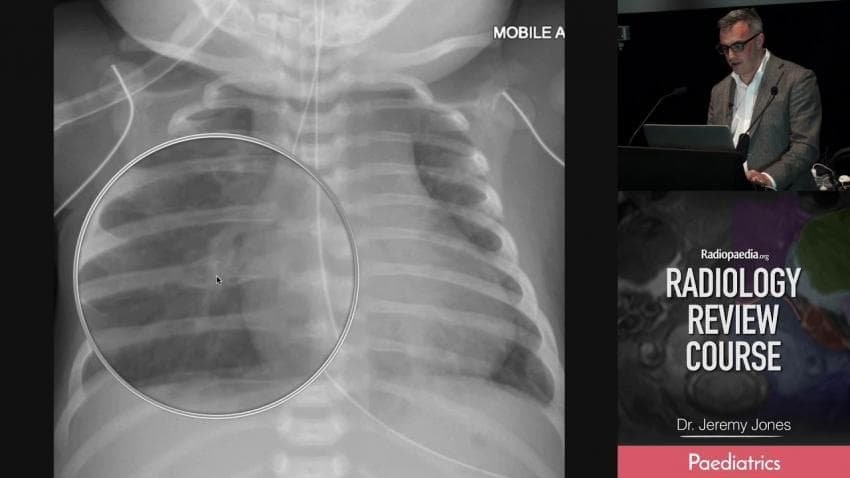

UFC)전 챔피언 메랍 5번 갈비뼈 완전골절

갈비뼈 부러지고 오라운드를 뛰다니.